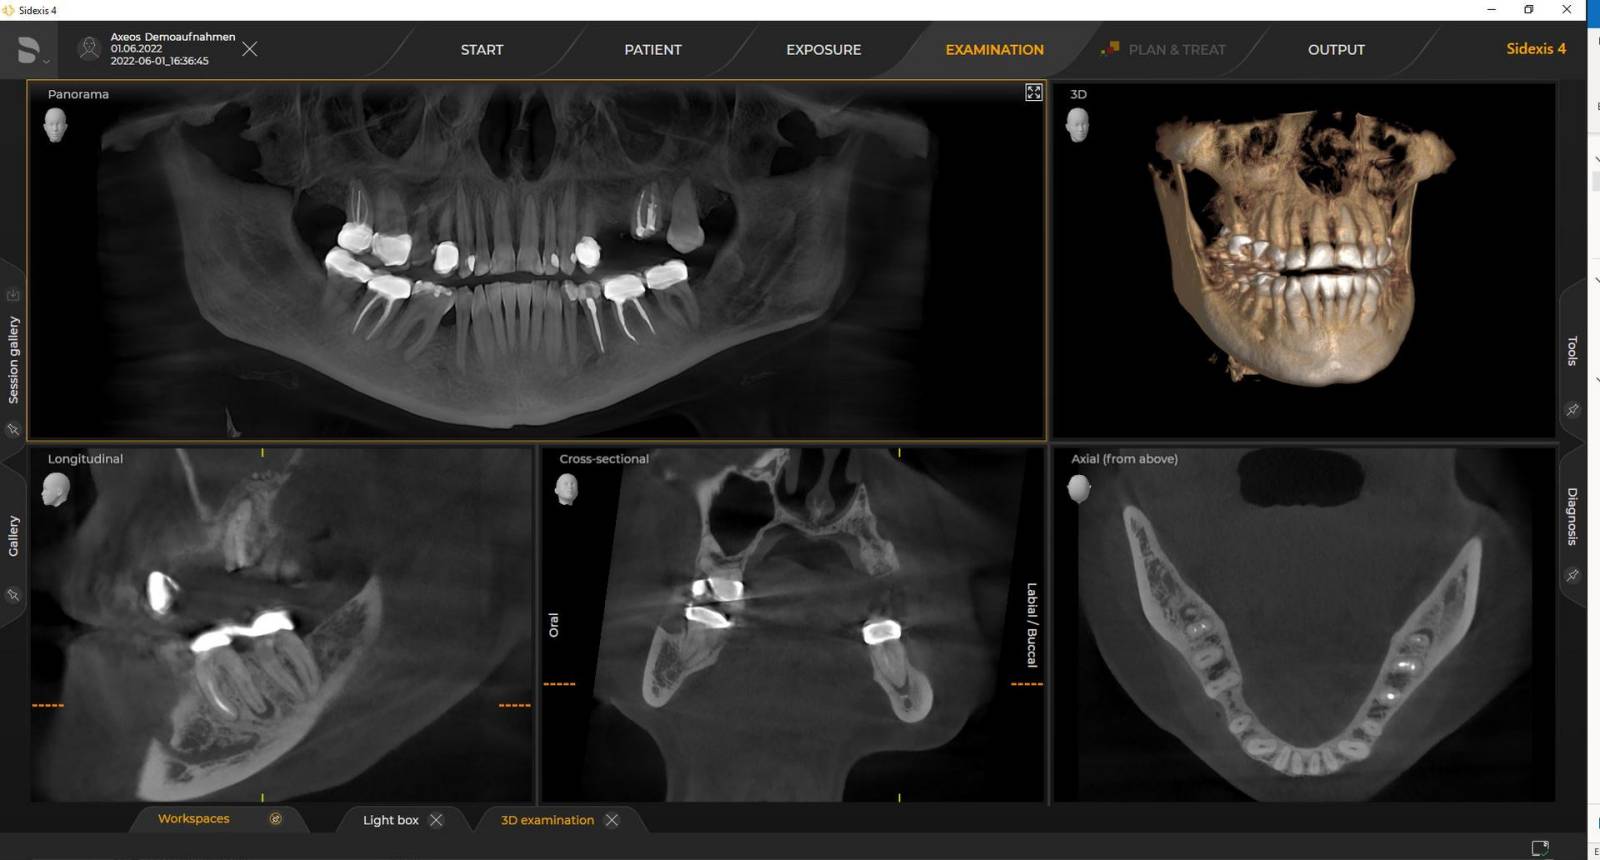

3Dレントゲン装置の参考画像

インテリジェントロードーズ

専用フィルターで最適化された低線量モードにより、大幅に低減された線量で骨などの密な構造の画像診断が可能になります。そのため、インテリジェントロードーズ機能は多くの臨床現場において有用で効率的な機能となります。歯列矯正でもインプラントでも、弊社のソリューションを使用することで、それぞれのケースでの最適な設定が可能です。

• 適応症に基づく低線量でのCT撮影は、さまざまな臨床状況に適しています

• 専用フィルターは、従来の低線量アプローチと異なります。弊社のインテリジェントロードーズ機能は、電流を下げるだけでなく専用の銅フィルターも採用しています。これにより、低線量にも関わらず、骨などの密な構造を高画質で確認が可能です。

• CT撮影において低線量モードを使用すると、被ばく線量を最小限に抑え、パノラマ撮影の際と同等の線量でCT画像が得られます。

デンツプライシロナ 3D機は、Sidexis 4でのみ動作します。しかし、Sidexis XGからSidexis 4へのデータの移行は非常に容易です。Sidexis 4を使うと、最新ツールを使用した完全なデジタル体験が可能になります。